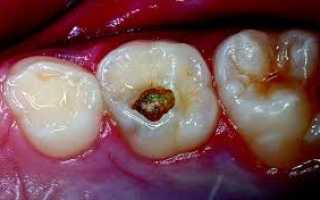

Для глубокого кариеса характерно наличие в зубе глубокой полости с пораженными микроорганизмами тканями, дно которой близко подходит к пульповой камере. В пульповой камере располагаются нервные окончания, воспалительный процесс оказывает воздействие на нервные волокна и зуб начинает болеть, реагируя на механические, химические и температурные манипуляции.

Отличительны симптомы при первичном и вторичном глубоком кариесе. Так, острая форма характеризуется узким входным отверстием в полость зуба и довольно широким основанием. Это делает больной зуб чувствительным к перепадам температур и химическим раздражителям (например, сладкой или кислой пище). Для хронической формы характерно широкое входное отверстие и узкое дно кариозной полости, поэтому основной дискомфорт человек испытывает при механическом воздействии на зуб (при зондировании, набивании пищи в кариозную полость, попытке самостоятельно извлечь остатки пищи).